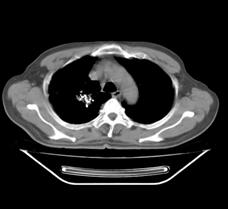

典型病例1:患者鞠xx,女,68岁,住院号:488141,因左胸痛1月余入院。2015年3月31日胸部增强CT示:左肺下叶2.5cmx2.8cm占位,左侧第三前肋骨溶骨性转移、形成厚约3cm肿块,左侧腋窝淋巴结2.1cmx4.1cm及前纵膈淋巴结转移。患者于2015年4月1日经CT引导下穿刺活检、病理证实为左肺下叶腺癌。于2015年4月5日对其采用125I放射性粒子置入治疗。治疗3个月随访,患者胸痛缓解,左肺下叶原发病灶消失,粒子聚集;左侧第三前肋骨基本恢复正常形态;前纵膈淋巴结消失,粒子聚集;左侧腋窝淋巴结缩小2/3。目前患者生活质量良好,可从事一般家务劳动。

术前CT片: